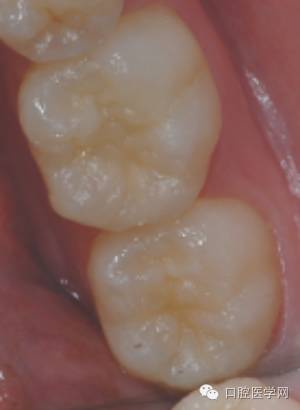

Z350树脂制作印章

要点

1、有效隔湿,棉卷或橡皮障

2 、轻吹牙面

3 、印章应覆盖所有需恢复形态的牙面

4、 印章需要有一定的厚度,否者易变性或取出时折裂。

固化 光照时间要够,充分固化

印章完成用探针将印章取下,接触面涂布凡士林,若菲边较多,可作适当修整